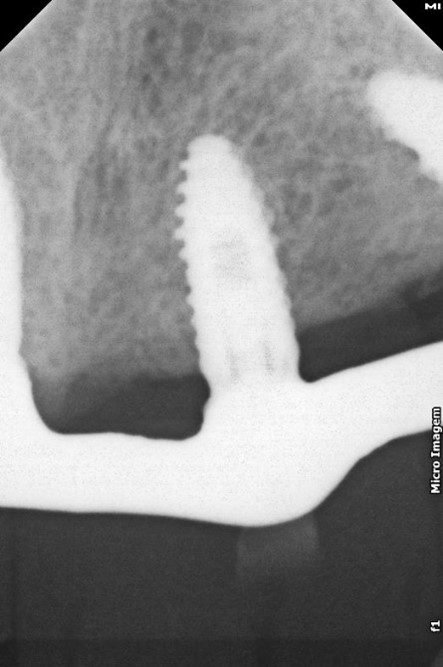

FIG. 14a b c d – Radiografia de acompanhamento de 26 meses após a cirurgia. (implante 11)

Após a perfuração inicial com broca lança de 15 mm para os implantes distais e 11 mm para os anteriores, a perfuração com broca 2,4 nos mesmos comprimentos. paralelizadores foram utilizados para verificar o polígono formado e a posição dos implantes. A perfuração seguinte com broca 3.4 e, após, com broca 3.9, a onde foi realizado subperfuração em comprimento (50%), garantindo melhor estabilidade primária. Foram instalados implantes Vezza de 4,3×15 mm na região posterior da maxila e de 4,3×11 mm na região anterior.

Todos os implantes atingiram um torque de 80 N, possibilitando a realização de carga imediata. Mini pilares retos com transmucoso de 2mm foram instalados nos implantes anteriores e mini pilares angulados de 30 graus com transmucoso de 3mm nos distais, corrigindo a ajuste dos implantes e sustentando o assentamento passivo da barra.